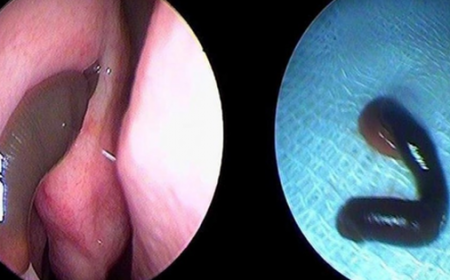

PHÁT HIỆN CON VẮT TRONG HỐC MŨI CÔ GÁI

Vừa qua tại Thái Nguyên, Một cô gái đi khám vì chảy máu cam thường xuyên, qua quá trình thăm khám bác sĩ đã phát hiện một con vắt dài 3cm được phát hiện trong...